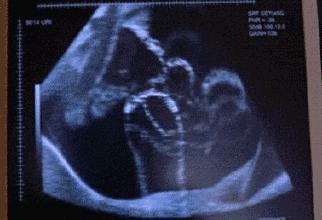

(仅配图用,不作任何医学参考)